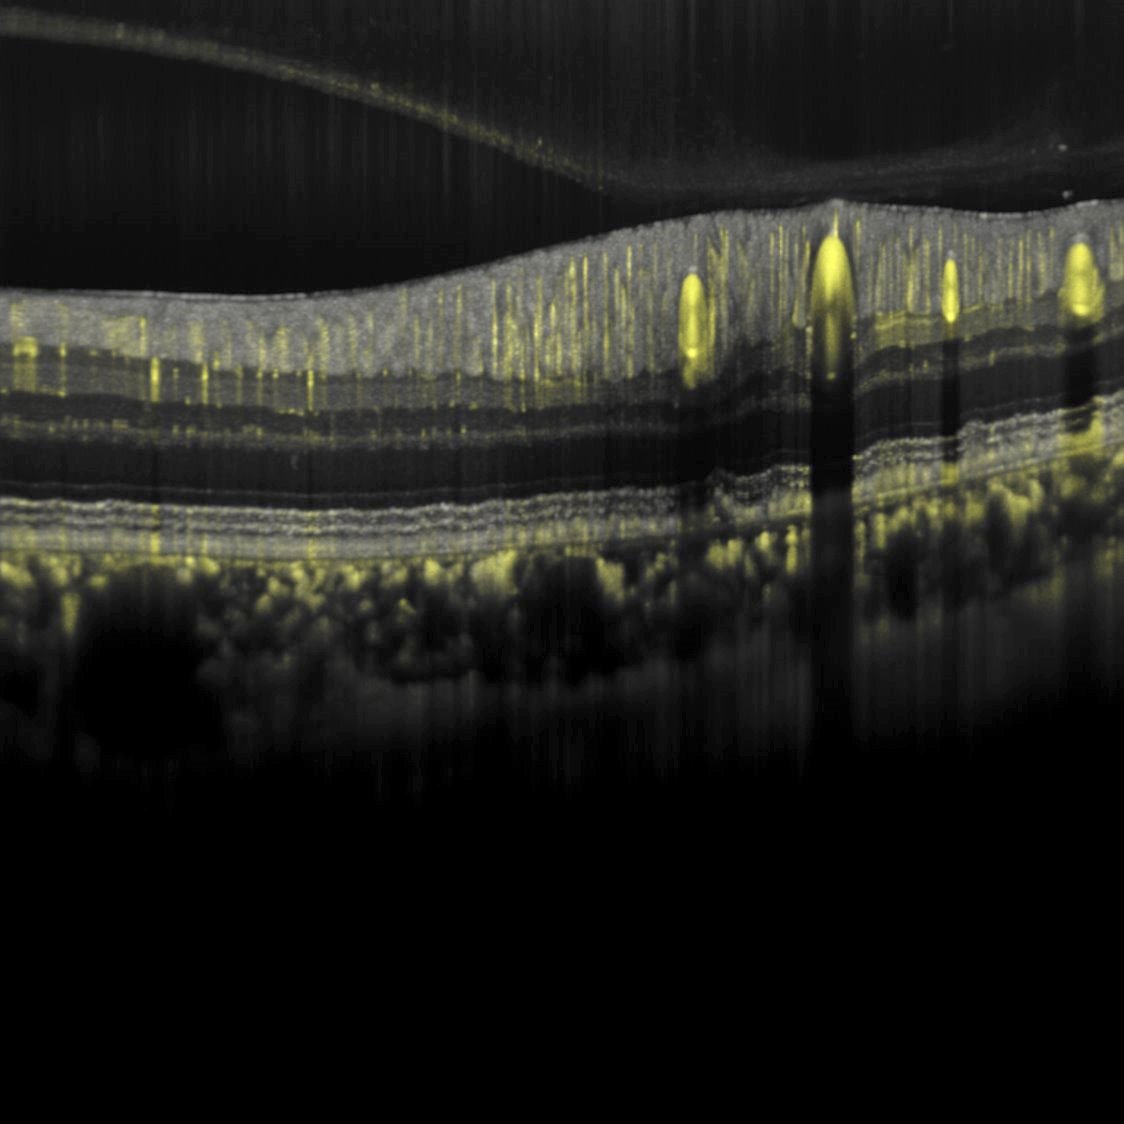

A Whole Eye montage composed of 5 images acquired using ANTERION and 6 images acquired using SPECTRALIS. Composite image deliberately not to scale for promotional purposes only.